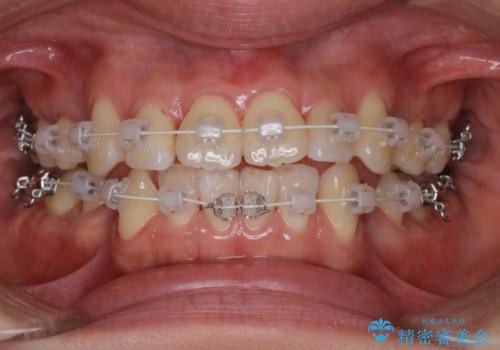

【審美装置】前歯のデコボコを綺麗に

- 上の前歯のデコボコが気になるということで来院されました。

叢生量(デコボコ)が多いため、上下左右4番目の歯を抜歯してワイヤー矯正を行う治療計画を立てました。

主訴である前歯のデコボコが改善され、噛みあわせも綺麗になりました。

歯肉退縮もなく、予定通りに治療を終えることができ良かったです。